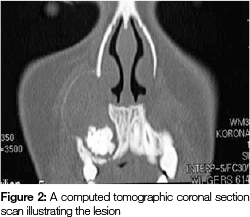

A computed tomographic scan was requested which revealed two separate lesions, one lying buccal and the other lying palatal. The buccal lesion was seen to be a well-defined unilocular radiolucency containing a radiopaque mass (Figure 2).